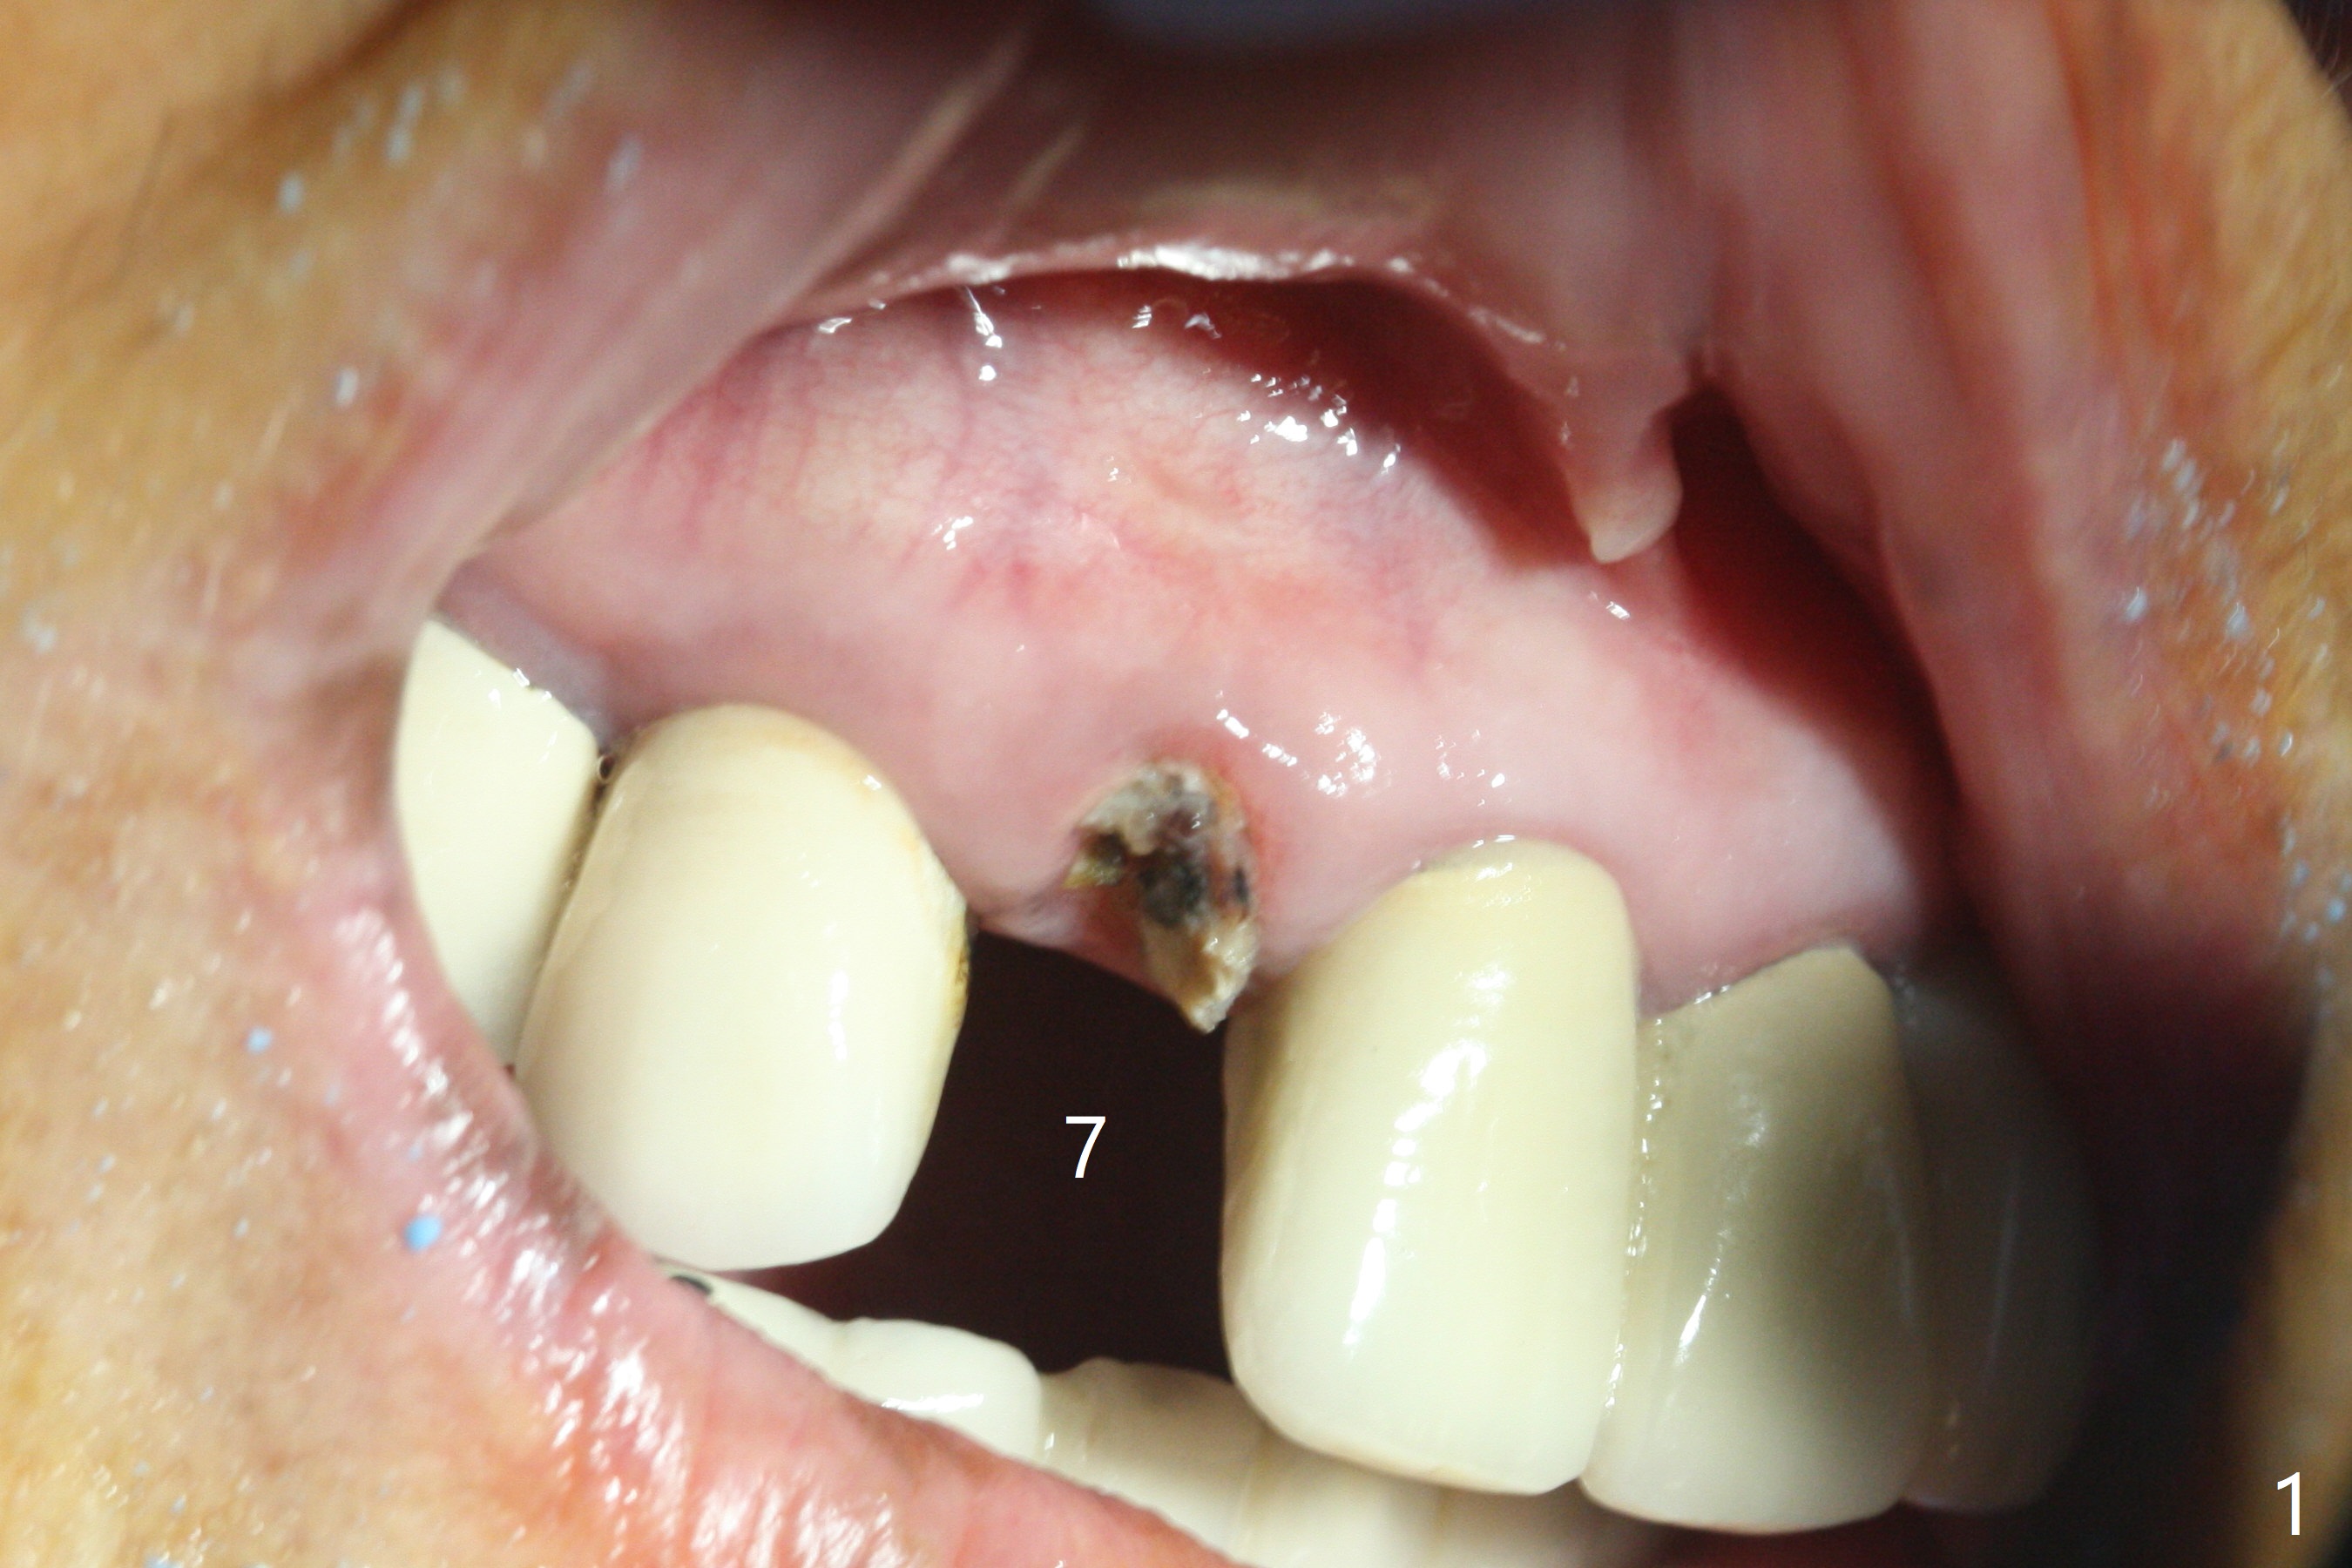

The edentulous area at #7 is narrow both buccopalatally and mesiodistally, whereas the crowns of the neighboring teeth are long (Fig.1,2). For the latter reason, it is difficult to remove the apical portion of the root, including gutta percha with surgical handpiece (Fig.3 *) for socket shield (Fig.2 *). To avoid the perspective implant touching socket shield, initial osteotomy is palatal. When a 2 mm drill is being used, the coronal end of the palatal plate starts to perforate. A 2.5x14 mm 1-piece implant is placed with 30 Ncm (Fig.4). The palatal plate is thin (Fig.5). Preop CT will help determine the position of initial osteotomy. The buccal gingiva seems to have been re-attached to the underlying alveolus and the provisional 1 month postop (Fig.6). The teeth #8 and 9 fracture (an implant is placed at #8 and bone graft at #9, while the implant at #7 is osteointegrating (Fig.7). In fact the shield is exposed without symptom. A year postop, another dental provider sends a photo of apparently hemorrhagic gingiva around #7 crown (Fig.8). A few days later with oral hygiene instruction, the gingiva around the exposed root piece is healthy (Fig.9). The root surface is reduced; with socket shield, there is no buccal plate collapse; in contrast the neighboring buccal plate (at #8 and 9) is concave (Fig.10). There is minimal exposure 11 days postop (Fig.11). The gingiva palatal to the shield is erythematous, a possible sign of periimplantitis. The socket shield at #7 appears to be fused with the buccal plate 11 months postop (Fig.12), as compared to the implant at #10 nearly 4 years postop (Fig.14). The buccopalatal widths at #7 and 10 are equivalent (Fig.13,15).